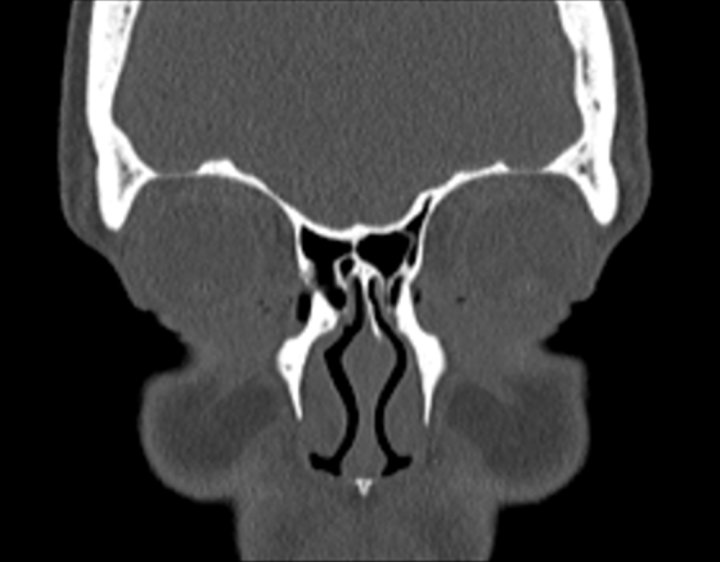

Click any image for labels.